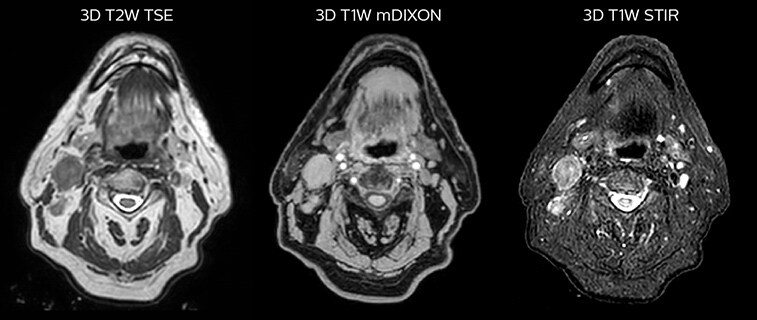

T2W 3D, 3D STIR and mDIXON MRI scans.

MR-based target contouring on 3D T2W TSE in transversal, sagittal and coronal planes.